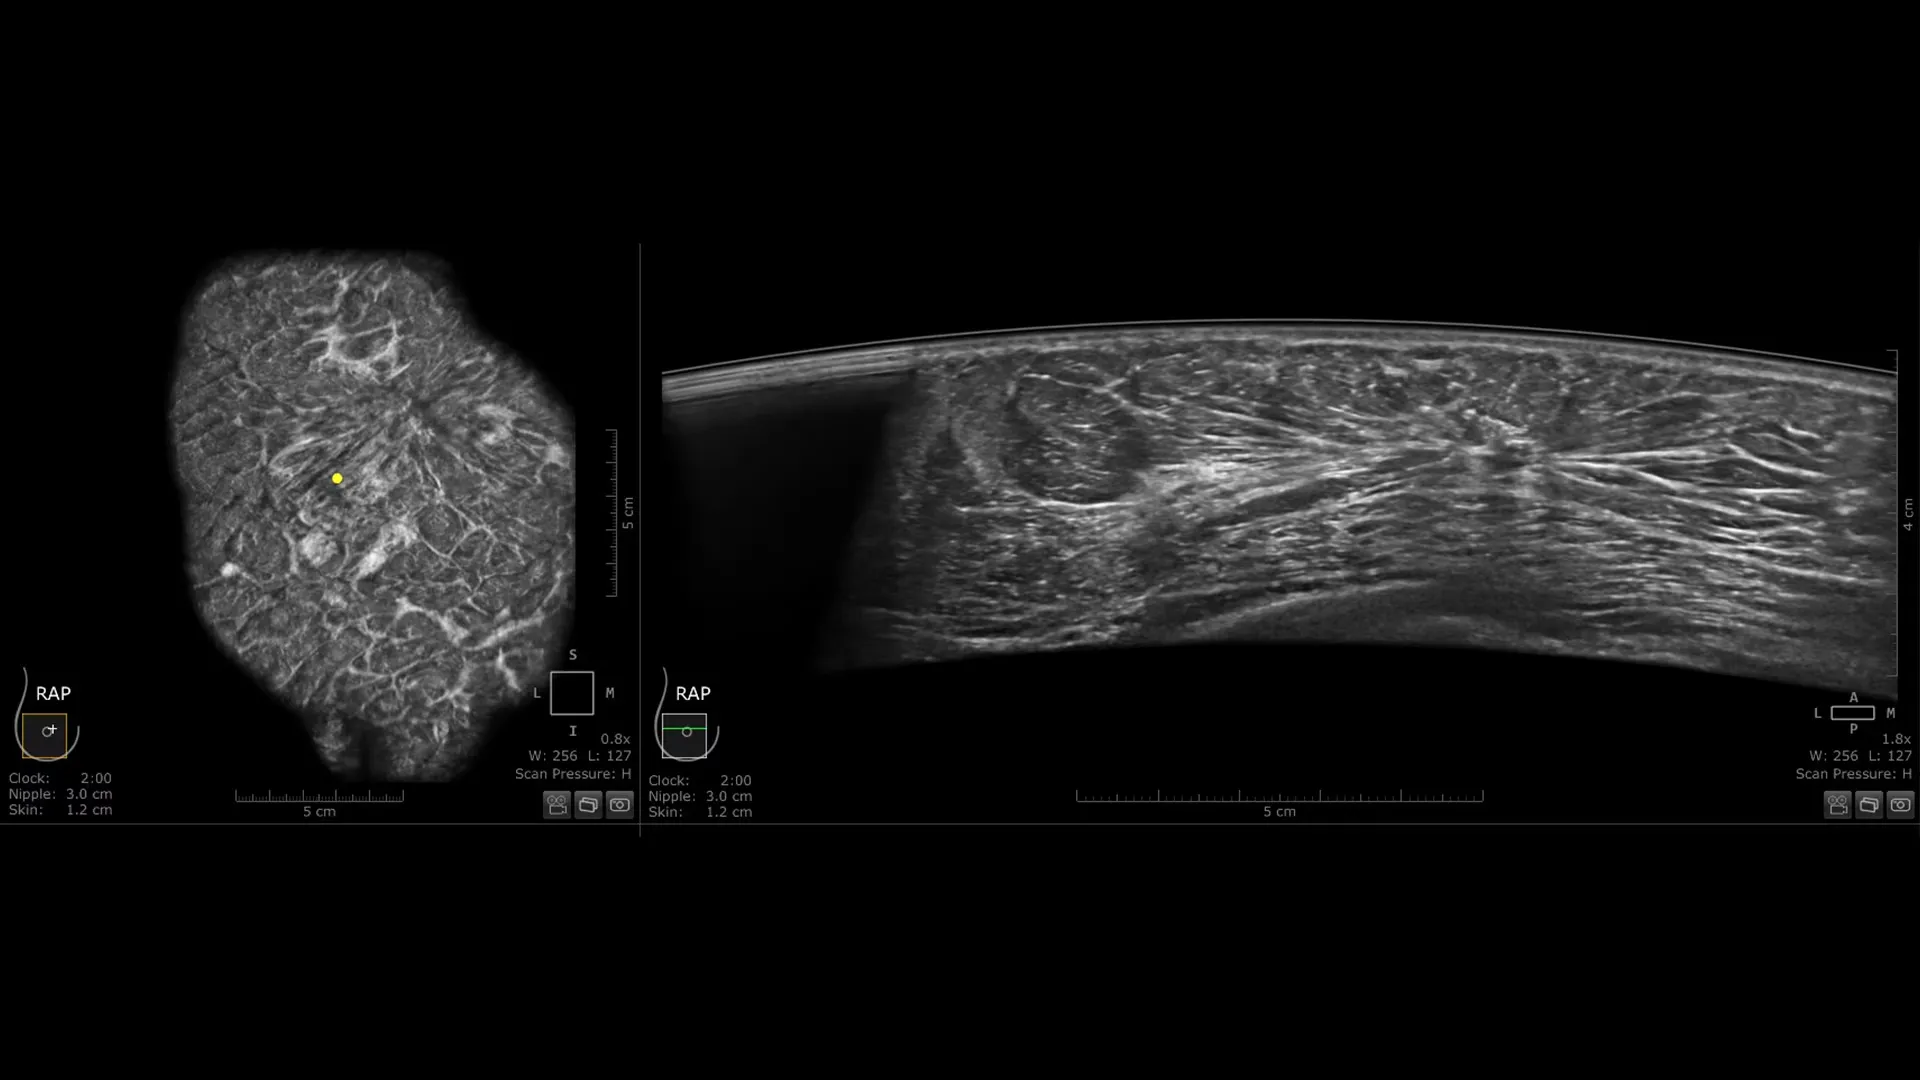

Invenia ABUS Premium osmišljen je za visoku propusnost pacijentica i iznimnu kvalitetu prikaza, pružajući visoku razinu dijagnostičke sigurnosti. Zahvaljujući inovativnom dizajnu, sustav je jednostavan za korištenje, reproducibilan, neovisan o korisniku, standardiziran te omogućuje očitanje nalaza s bilo koje lokacije.

Nova Reverse Curve™ sonda za poboljšane performanse

Njezin blago zakrivljen oblik duljine 15,3 cm prati prirodnu konturu dojke, povećavajući udobnost pacijentice* i osiguravajući potpuni kontakt za sveobuhvatnu pokrivenost. Unaprijeđena kvaliteta prikaza* dodatno povećava dijagnostičku sigurnost pri očitanju ABUS pregleda.

Izvrsna kvaliteta prikaza i 40% brže skeniranje

- cSound Imageformer, softverska obrada slike, omogućuje iznimno precizan i ponovljiv prikaz zahvaljujući automatskom fokusiranju u svakoj točki slike